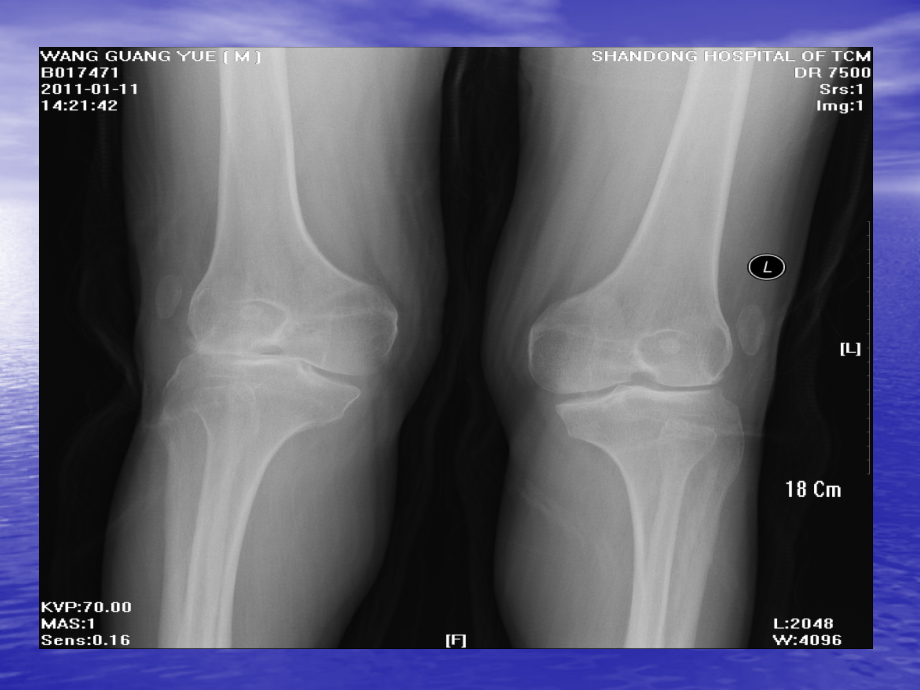

单击此处编辑母版标题样式,单击此处编辑母版文本样式,第二级,第三级,第四级,第五级,*,男,46岁。因双膝疼痛就诊。,体检:双侧拇指指甲发育不良,有纵裂。双侧髂骨后缘可触及骨性突起。其父有类似指甲改变。,甲髌综合征(,nail-patella syndrome,,,NPS,)是一种罕见的常染色体显性遗传性疾病,主要临床特征为“四联征”:指甲发育不良、髌骨发育不良或缺如、髂骨角和桡骨小头脱位。,98%,的患者有指甲发育异常,,70%,有髂骨角,,30%,60%,有肾病,,15%,发展为肾功能衰竭。严重的肾损害是本病致死的重要原因。,临床表现,(,1,)指甲改变:指甲发育不良是诊断,NPS,的特异性征象。包括指甲角化不良,指甲小而扁,中央呈“勺”形凹陷,可见纵裂。,(,2,)骨骼改变:骨盆出现髂骨角。膝部不适,行走不稳、疼痛。膝关节弯曲畸形,伸直受限。髌骨易脱位。肘关节屈曲、伸直受限,不能旋前、旋后。,(,3,)眼部表现。可有青光眼、白内障等。,(,4,)肾脏病变。蛋白尿、血尿,偶可发生肾功能衰竭。,